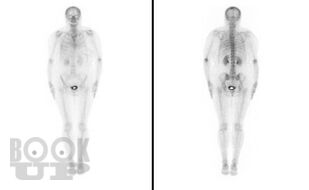

Метастазы в костную ткань у пациентов при онкоурологической патологии

Учебное пособие подготовлено в соответствии с требованиями ФГОС ВО 3++ по программе подготовки кадров высшей квалификации в ординатуре по специальности 31.08.68 Урология (2014). В пособии на современном уровне излагаются механизмы распространения метастазов в костную ткань, их диагностика и лечение у пациентов с онкоурологической патологией. Пособие содержит рисунки из открытых источников интернета.